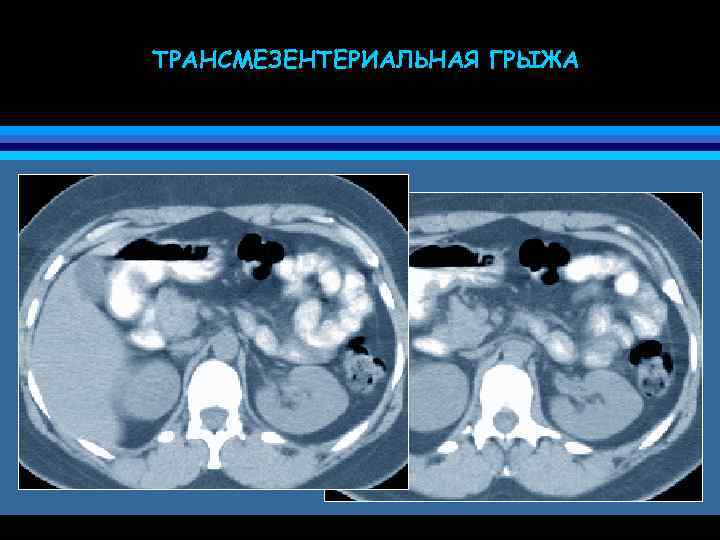

ТРАНСМЕЗЕНТЕРИАЛЬНАЯ ГРЫЖА • грыжа через брыжейку (или большой сальник) • трудности дифференциальной диагностики со спаечной непроходимостью и заворотом • причина дискомфорта и болей в животе (частичная непроходимость кишечника) • узлообразования

ТРАНСМЕЗЕНТЕРИАЛЬНАЯ ГРЫЖА